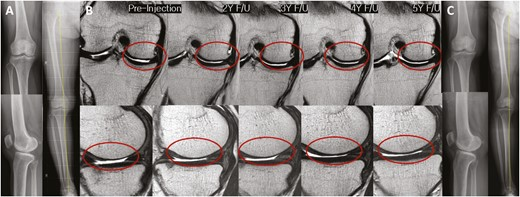

2022年5月14日,韓國(guó)江東慶熙大學(xué)醫(yī)院骨科在行業(yè)期刊《干細(xì)胞轉(zhuǎn)化醫(yī)學(xué)》上發(fā)表了一篇關(guān)于《關(guān)節(jié)內(nèi)注射間充質(zhì)干細(xì)胞治療膝骨關(guān)節(jié)炎的安全性和有效性:5年隨訪研究》的研究成果。【4】

關(guān)節(jié)內(nèi)注射間充質(zhì)干細(xì)胞治療膝骨關(guān)節(jié)炎的安全性和有效性:5年隨訪研究

招募了11名膝關(guān)節(jié)骨關(guān)節(jié)炎患者,并在單次關(guān)節(jié)內(nèi)注射自體高劑量 (1.0×108?) ADMSCs 的5年隨訪期間進(jìn)行了系列評(píng)估。

2.放射學(xué)結(jié)果評(píng)估

• 注射后5年內(nèi)未見內(nèi)翻力線或KL等級(jí)分布明顯惡化(圖3)。

• 系列MRI檢查顯示,注射后3年內(nèi)MFC軟骨缺損面積呈減少趨勢(shì),治療后5年內(nèi)未見明顯惡化(圖 4)。

• 內(nèi)側(cè)間室軟骨WORMS評(píng)分在注射后2至3年間均有明顯改善(2年,P=0.029;3年,P=0.031)(表3)。

• 治療后3年內(nèi),總體WORMS顯示出顯著改善,從73.4±27.8顯著下降至70.5±26.8(6個(gè)月;P= 0.020)、65.5±29.4(2年,P=0.016)和66.5±30.7(3年,P=0.041)(表3)。

• WORMS子評(píng)分還顯示,在注射后2至3年內(nèi)、注射后2年內(nèi)和注射后3年內(nèi),總軟骨狀態(tài)、骨髓水腫和滑膜炎均有顯著改善。

綜上所述,VAS和總WOMAC評(píng)分在注射后6個(gè)月以及直到最新隨訪時(shí)均顯著改善??俉ORMS在注射后3年內(nèi)顯著改善。

單次關(guān)節(jié)內(nèi)注射自體高劑量ADMSCs可在5年內(nèi)提供安全的臨床改善,且不會(huì)出現(xiàn)放射學(xué)加重。此外,骨關(guān)節(jié)炎膝關(guān)節(jié)的結(jié)構(gòu)變化在長(zhǎng)達(dá)3年的時(shí)間內(nèi)顯示出顯著改善,這表明它可能是膝關(guān)節(jié)OA患者的疾病改良治療的一種可能選擇。